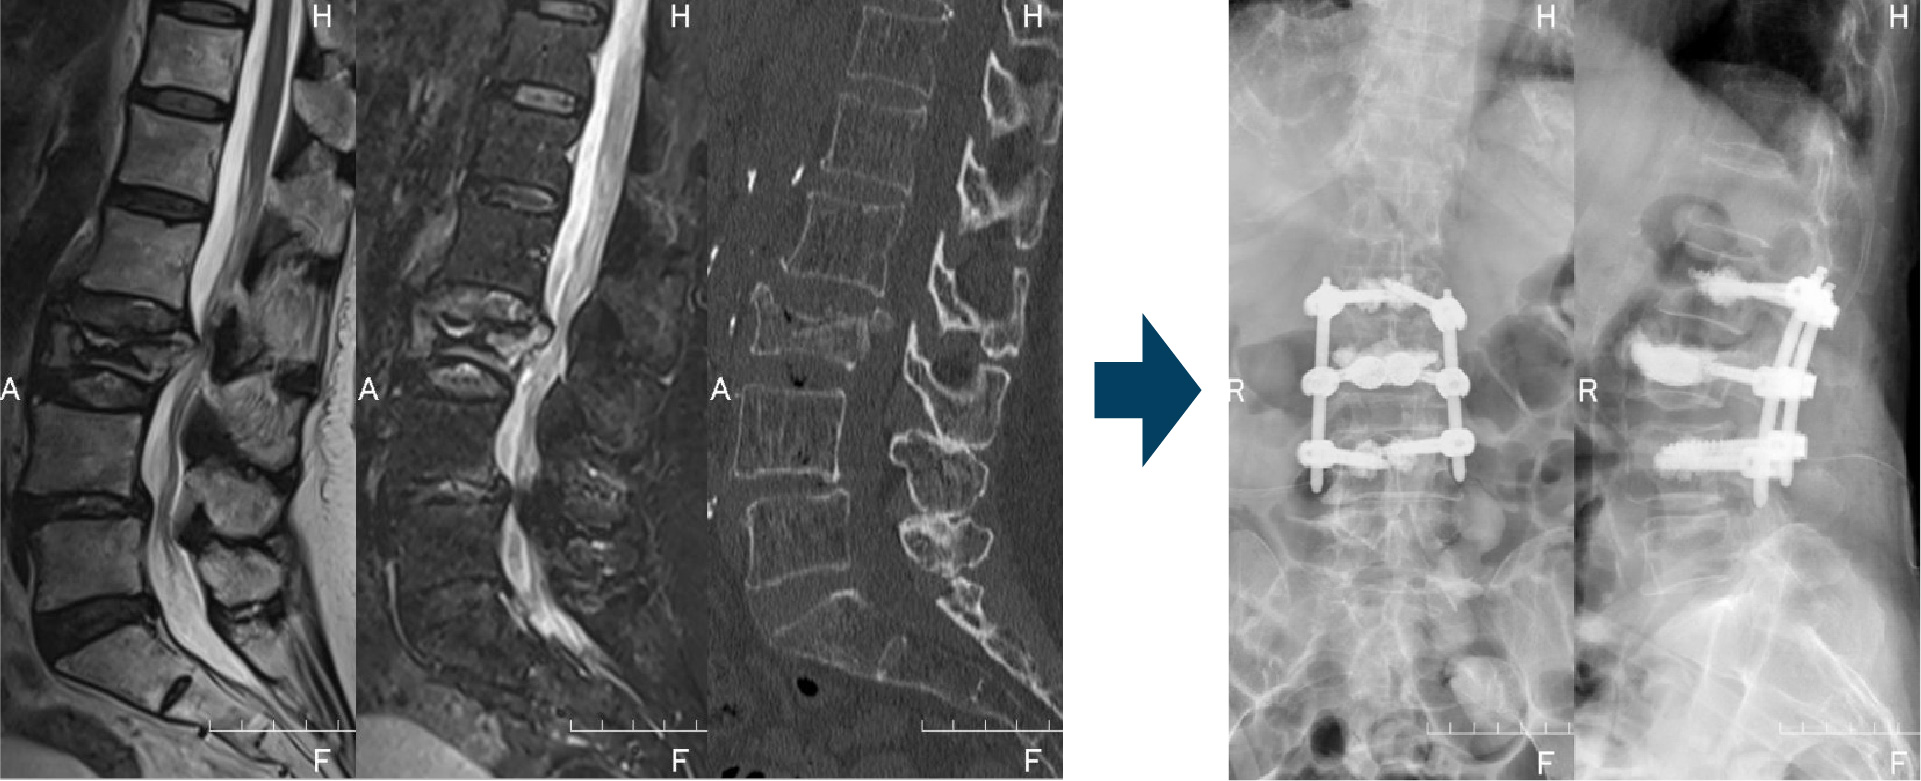

【第2腰椎圧迫骨折に対するBKPの実例】

転倒後発症した高齢者。術前、保存治療で腰痛の改善が乏しく、ベッドから起き上がることができませんでしたが、術後早期に疼痛は軽減し、歩行が可能となりました。